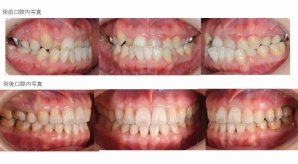

¥¤¥ó¥¹¥¿¥°¥é¥à¤ËºÜ¤»¤Æ¤¤¤ëÅö±¡¤Î¾ÉÎã¤Ç¤¹